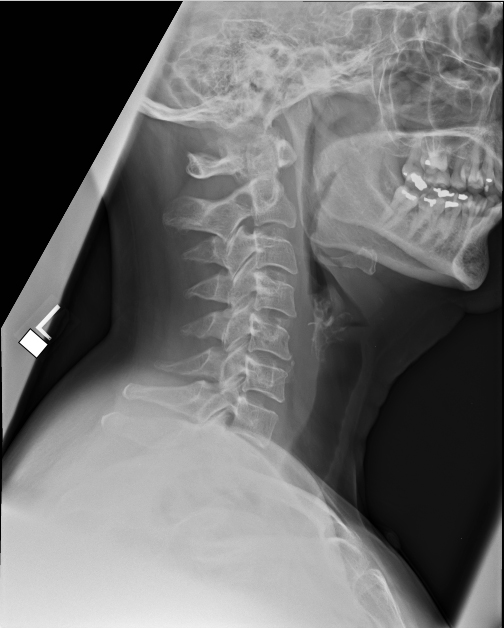

| 1 |

Normal |

Abnormal Right inferior orbital wall fracture (right orbital emphysema) |

Incorrect |